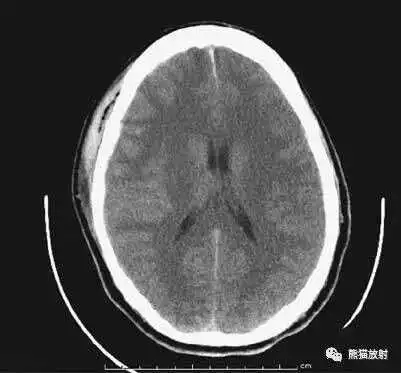

颅脑CT常用的三个窗(图A-C):

- 图B:脑窗(the brain window)

图B:脑窗;可清晰显示灰白质,可发现中风的早期征象或其他导致脑水肿等表现的病变。